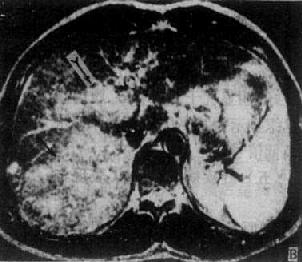

肝癌

图4-3-6 肝癌(MRI)

A、T1WI肝右叶可见大块较低信号区,其内信号不均,轮廓不规

则(↓)。门静脉内可见相同信号强度影像,为癌栓所致(↓)

B、T2WI上述稍低信号区成为稍高信号区(↓),门静脉内癌栓的信

号也增强(↓)